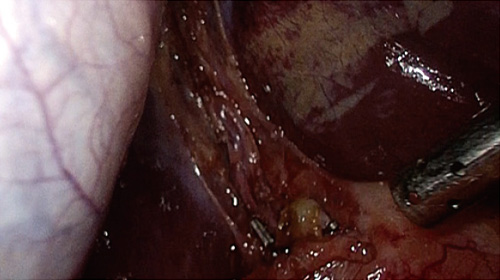

ソニーマーケティング株式会社(本社:東京都港区、代表取締役社長:川口大輔、以下、ソニーマーケティング)は、HDR(ハイダイナミックレンジ)信号に対応し、Mini LEDバックライトと独自のローカルディミング(部分駆動)技術により高輝度・高コントラストを実現した医療用の31.5型4K液晶モニターを発売します。様々な医療映像を高精細・高画質で細部までクリアに映し出せる本機は、高い精度が求められる手術や検査時の視認性向上に貢献します。

31.5型4K(3840×2160ピクセル)の高解像度LCDパネルとMini LEDバックライトを搭載しています。細かいエリアでの明暗調整が可能になり視認性が向上することに加え、バックライトに独自のローカルディミング(部分駆動)技術を用いて、高いピーク輝度(1850cd/㎡)と100万:1の高コントラスト比を実現しています。

モニター前面に内蔵した明るさセンサーが手術室内の照明環境を検知して、モニターの明るさを自動的に調整します。手術中にICG*を使用するなど、暗い照明へ変化するケースでも視認性を確保することができます。